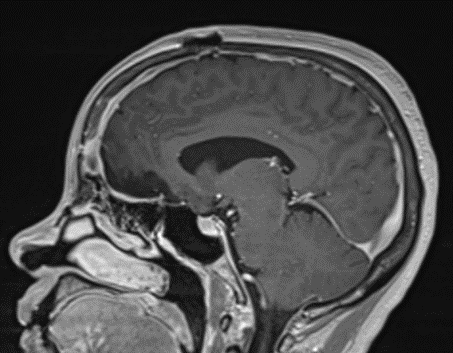

Figure 1b – Postoperative MRI demonstrating a complete resection without residual enhancement.

She was started on high-dose steroid and antiseizure prophylactic medicine. Surgical intervention was offered for mass effect, symptomatic relief, neurologic preservation, and histopathologic diagnosis. Dr. Gaudin performed a bifrontal craniotomy with complete resection of neoplasm through an interhemispheric and subfrontal approach. Postoperative imaging demonstrated a gross total resection without residual tumor and resolution of mass effect (Figure 1b and 2b). Intraoperative pathology was consistent with meningioma, WHO grade 1. She recovered very well, and was discharged home on postoperative day 3. On her follow-up outpatient visit, her preoperative symptoms had fully resolved, and her olfactory sense was maintained.